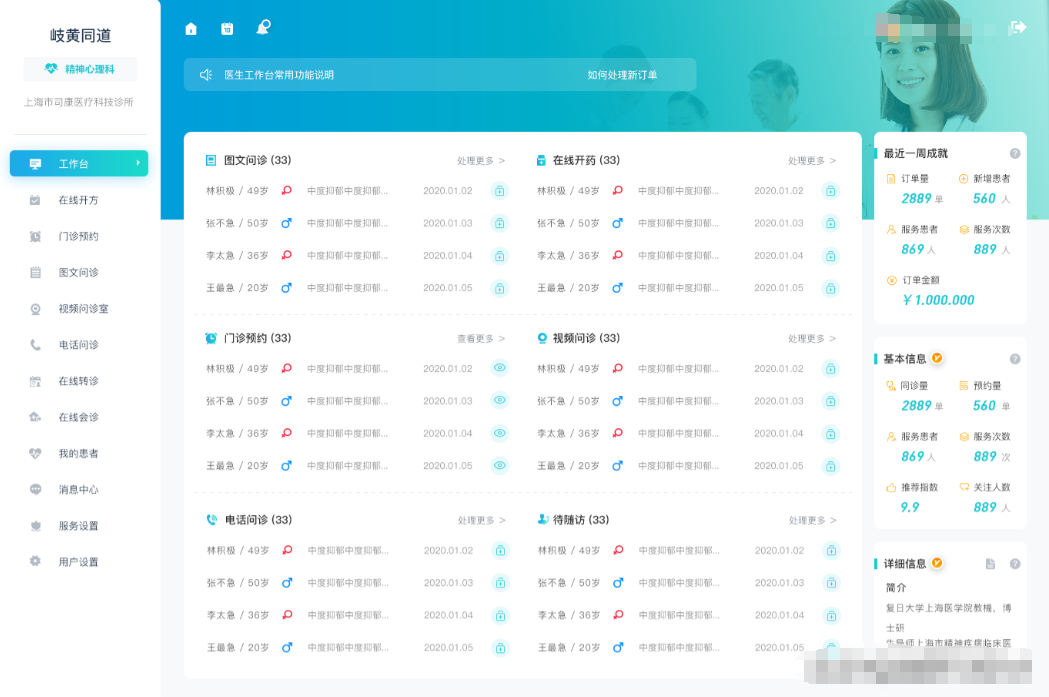

二、电子病历系统(EMR)的优势及发展趋势

电子病历系统(EMR)是医疗信息化的核心,它取代了传统的纸质病历,实现了病历的数字化管理。

EMR 系统的优势主要体现在以下几个方面:首先,提高了病历的书写效率和质量。医生可以通过电子病历系统快速录入病历信息,避免了手写病历的繁琐和错误。同时,系统还可以提供病历模板、智能提示等功能,帮助医生规范病历书写,提高病历的质量。其次,方便了病历的存储和查询。电子病历可以存储在服务器中,不会因为时间和空间的限制而丢失。患者和医生可以通过系统随时查询病历信息,方便快捷。再次,促进了医疗信息的共享和交流。电子病历系统可以与其他医疗信息系统进行对接,实现医疗信息的共享和交流。医生可以通过系统查看患者在其他医院的病历记录、检查检验报告等,为诊断和治疗提供参考。最后,有助于医疗质量的控制和管理。电子病历系统可以对病历的书写质量、医疗行为的规范性等进行监控和管理,提高医疗质量和安全。

随着信息技术的不断发展,电子病历系统也在不断演进。未来,电子病历系统将更加智能化、个性化和移动化。智能化方面,系统将利用人工智能技术,实现病历的自动分析、诊断建议等功能。个性化方面,系统将根据患者的病情和需求,为患者提供个性化的医疗服务和健康管理方案。移动化方面,系统将支持移动设备的访问,方便医生随时随地查看病历信息和进行医疗服务。